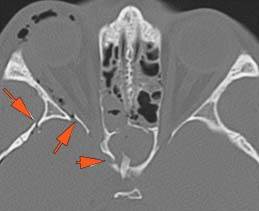

Right Temporal Bone

The external auditory canal shows abnormal soft tissue thickening.

The roof of the mastoid and/or middle ear is fractured.

A possible meningocele and/or encephalocele or CSF leak is present.

The ossicles, in particular the incus long process, the incudostapedial joint and stapes are fractured or dislocated.

The facial canal including the labyrinthine, tympanic and descending portions and nerve are fractured.

The inner ear including the lateral semicircular canals, vestibule and/or cochlea is fractured or otherwise abnormal.

There is subperiosteal, epidural or subdural hematoma along the roof of the mastoid or middle ear or the superior and posterior (intracranial) surfaces of the petrous portion of the temporal bone.

Left Temporal Bone